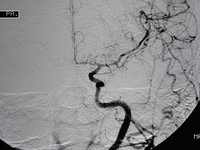

SWIFT PRIME试验表明,在急性缺血性卒中患者中,对大血管前循环闭塞的患者予以溶栓治疗和Solitaire FR(血流恢复)支架取栓术治疗可减少3个月时卒中致残率并增加患者存活比例和功能独立性。洛杉矶UCLA综合卒中中心的Jeffrey Saver博士在2015年国际卒中大会(ISC)上呈现了这些结果。

对于近端脑动脉闭塞的缺血性卒中患者(存在可挽救性组织)而言,与单独使用阿替普酶相比,采用支架取栓更能改善患者预后。这项研究于2月11日呈现在2015年国际卒中大会上,并同时在线发表于《New England Journal of Medicine》。